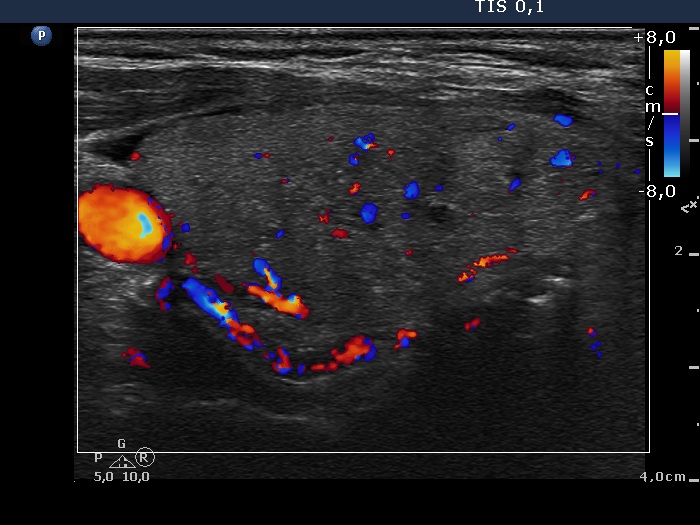

Ultrasonography. The thyroid was echonormal. Both lobes had multiple small discrete lesions, partly echonormal, partly moderately hypoechogenic. There were no nodules of oncological significance.